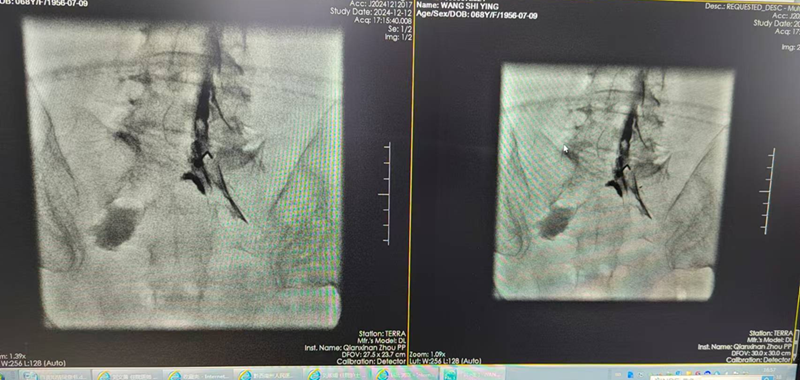

能完成该标准要求的绝大多数手术,包括选择性神经根阻滞技术、交感神经丛(干)介入医治技术、颅神经介入医治技术、神经射频调制技术、腰椎间盘介入医治技术、颈椎间盘介入医治技术、外周神经射频技术、脊髓电刺激、椎体成形术、硬膜外造影术、椎间盘造影术等。

交感神经丛(干)介入医治技术

硬膜外造影术